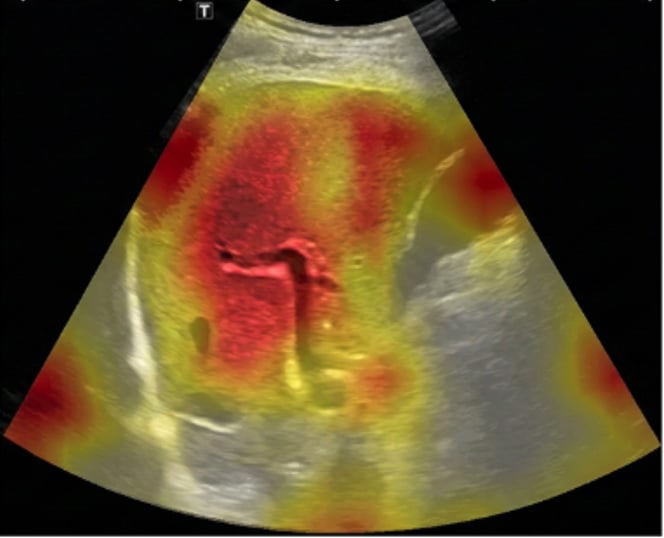

“นาโน” บอกว่า SmartLiva ทำงานเหมือนอัปเกรดจากภาพอัลตราซาวด์ขาวดำธรรมดาให้กลายเป็นผลวินิจฉัยที่อ่านง่ายและแม่นยำ โดยแพทย์อัปโหลดภาพผ่านเว็บได้ทั้งบนคอมพิวเตอร์หรือแท็บเล็ต จากนั้นระบบจะช่วยปรับภาพให้ชัดขึ้น คัดเฉพาะบริเวณเนื้อตับที่ต้องวิเคราะห์ และทำให้ภาพดูเข้าใจง่ายขึ้นด้วยการไฮไลต์เป็นสี เช่น ตับเป็นสีแดง ไขมันเป็นสีเหลือง เพื่อให้เห็นความผิดปกติได้ทันที โดย AI จะทำการประเมิน 3 เรื่องพร้อมกัน คือ ประเมินระดับพังผืด/ความแข็งของตับ (F0–F4), ตรวจหาความผิดปกติของเนื้อเยื่ออย่างถุงน้ำหรือมะเร็งตับ และตรวจหาพยาธิใบไม้ตับ ซึ่งตัว AI จะทำการประมวล วิเคราะห์ และสรุปผลออกมาเป็นรายงานพร้อมภาพประกอบและคำอธิบายที่คนทั่วไปเข้าใจได้ โดย AI ทั้งหมดถูกฝึกฝน (Train) ด้วยฐานข้อมูลภาพอัลตราซาวด์กว่า 50,000 ภาพ จากโรงพยาบาลชั้นนำ อย่างโรงพยาบาลขอนแก่น โรงพยาบาลจุฬาลงกรณ์ และโรงพยาบาลรามาธิบดี